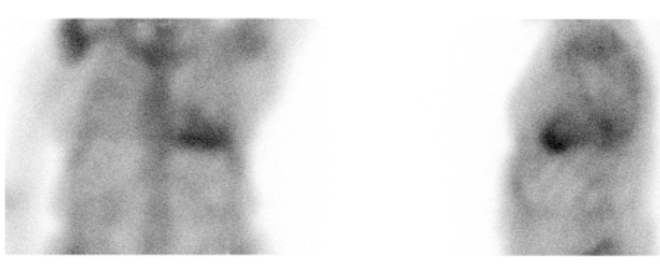

/ Obr. č. 1: Statická scintigrafie hrudníku v přední a levé boční projekci. Vyšetření 3 hodiny po aplikaci radiofarmaka.

Na planárních scintigramech a na tomografických řezech prokazujeme výrazně patologicky zvýšenou koncentraci radiofarmaka v myokardu levé srdeční komory.

Stupeň akumulace dle vizuálního skóre - Grade 3.

Závěr: Nález svědčí pro patologicky zvýšenou akumulaci radiofarmaka v myokardu.

Nález potvrzuje transthyretinovou srdeční amyloidózu.